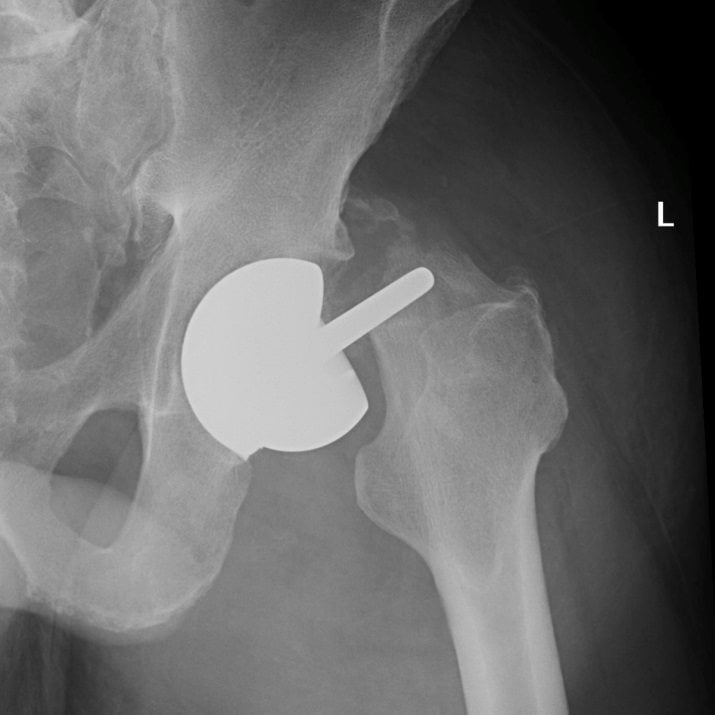

Эндопротезирование тазобедренного сустава может быть полным (тотальным) или частичным. В последнем случае выполняется только замена головки бедренной кости имплантатом.

Тотальное эндопротезирование — технически сложное хирургическое вмешательство. В ходе операции удаляются хрящевые ткани и субхондральные костные структуры, суставные поверхности подготавливаются для установки искусственной вертлужной впадины и головки бедренной кости.